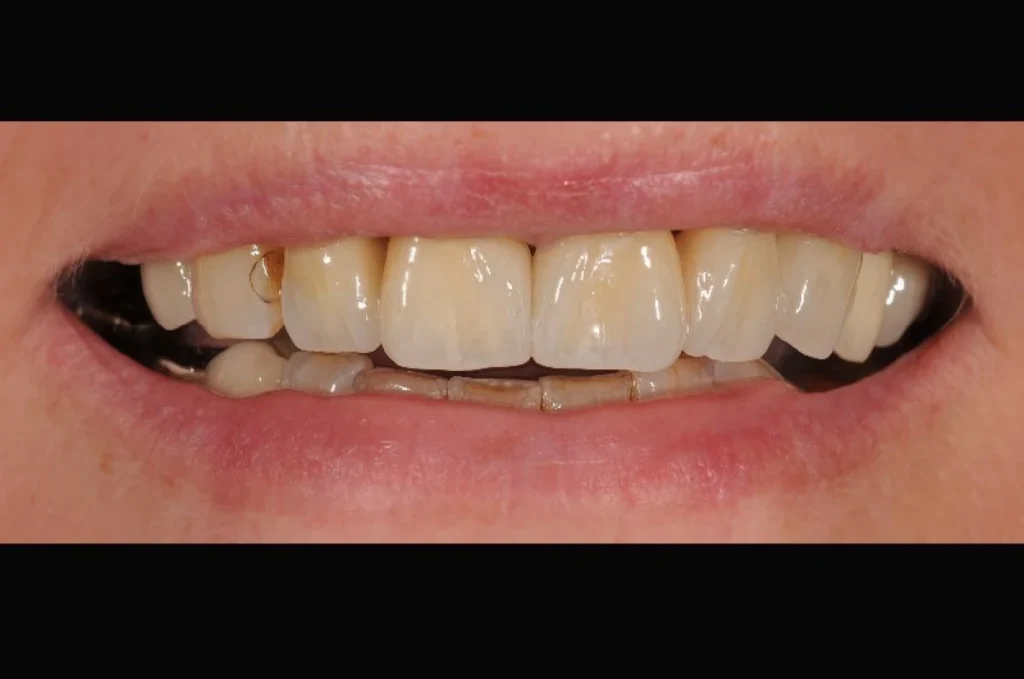

Découvrez nos cas cliniques

La prothèse conjointe est une solution incontournable pour restaurer dents, sourire et confiance. Elle représente un équilibre entre fonction, confort et esthétique.

La prothèse conjointe ne se limite pas à restaurer la fonction masticatoire. Elle contribue aussi fortement à l’esthétique et au bien-être psychologique. Retrouver un sourire harmonieux redonne confiance au patient, tant dans sa vie personnelle que professionnelle.

Nous attachons donc une attention particulière à l’intégration esthétique de chaque prothèse. La forme, la teinte et la translucidité sont soigneusement étudiées pour s’harmoniser avec les dents naturelles et offrir un rendu discret et naturel.